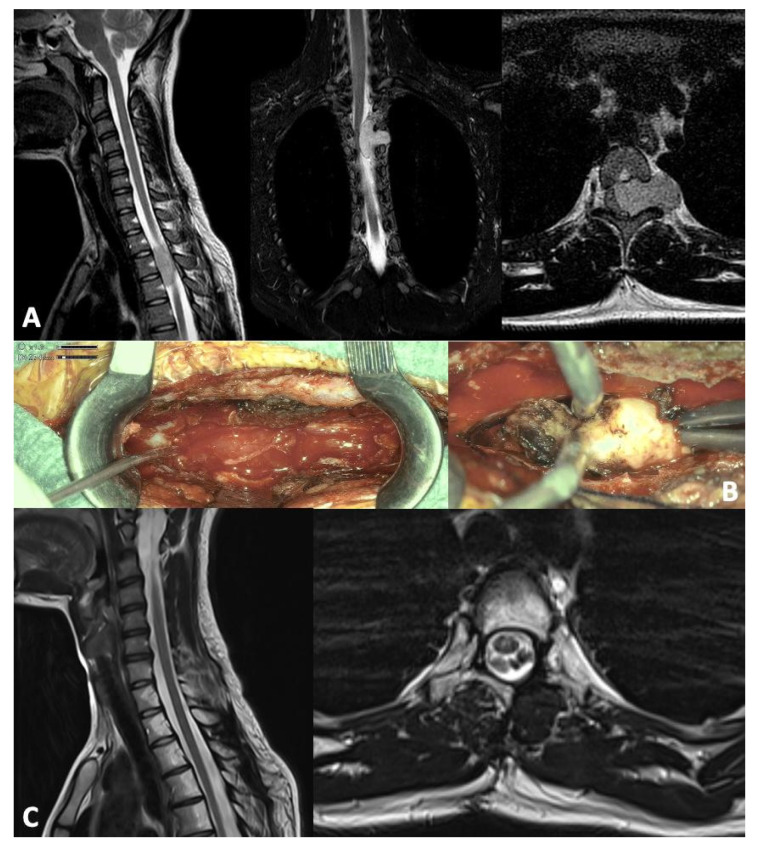

背景:脊柱孤立性纤维性肿瘤(SFTs)是一种罕见的肿瘤实体,在儿科人群中几乎是轶事。他们有很高的复发率,代表了一个持续的肿瘤挑战。方法:在这篇文章中,我们从一个病例报告开始进行了系统的回顾,以强调目前在治疗这些肿瘤方面的最新进展。结果:脊髓孤立性纤维性肿瘤(SFTs)是一种罕见的生长缓慢的肿瘤,可发生在髓内或髓外。只有有限数量的研究关注于原发性小儿脊髓定位。文献记载了5例小儿脊柱SFT病例。在MRI上,它们通常表现为高度血管化,对比度增强的肿块。组织学上,它们由胶原基质中的梭形细胞组成,具有鹿角状血管。更具侵袭性的亚型,如去分化SFTs,类似于高级别肉瘤。NAB2-STAT6融合是驱动EGFR信号、胶原生成和纤维化的关键标志物。其他诊断标志物包括CD34、CD99和Bcl-2。手术切除仍是主要治疗方法。在转移性病例中,化疗-主要是蒽环类药物,达卡巴嗪或替莫唑胺-被采用,尽管没有标准化的儿科方案存在。抗血管生成药物,包括酪氨酸激酶抑制剂,已经显示出前景。放疗用于术后局部疾病控制,但其对生存的影响仍在调查中。结论:手术仍然是治疗的基石,对疾病的自然病程和症状控制有重要影响。虽然在成人中探索放疗和化疗的临床试验正在进行中,但尚未为儿科患者建立特定的治疗方案。

Background: Spinal solitary fibrous tumors (SFTs) are a rare oncological entity, almost anecdotal in the pediatric population. They have a high relapse rate and represent an ongoing oncological challenge. Methods: In this article, we conducted a systematic review starting from a case report to highlight the current state of the art in managing these tumors. Results: Spinal solitary fibrous tumors (SFTs) are rare, slow-growing neoplasms that can be either intra- or extramedullary. Only a limited number of studies focus on primary pediatric spinal cord localization. Five pediatric cases of spinal SFT have been documented in the literature. On MRI, they typically present as highly vascularized, contrast-enhancing masses. Histologically, they are composed of spindle-shaped cells within a collagenous stroma featuring staghorn-shaped blood vessels. More aggressive subtypes, such as dedifferentiated SFTs, resemble high-grade sarcomas. The NAB2-STAT6 fusion is a key marker, driving EGFR signaling, collagen production, and fibrosis. Additional diagnostic markers include CD34, CD99, and Bcl-2. Surgical resection remains the primary treatment. In metastatic cases, chemotherapy-mainly with anthracyclines, dacarbazine, or temozolomide-is employed, although no standardized pediatric protocols exist. Anti-angiogenic agents, including tyrosine kinase inhibitors, have shown promise. Radiotherapy is used postoperatively for local disease control, but its impact on survival is still under investigation. Conclusions: Surgery remains the cornerstone of treatment, significantly impacting the natural history of the disease and symptom control. While clinical trials exploring radiotherapy and chemotherapy are ongoing in adults, no specific treatment protocol has been established for pediatric patients.